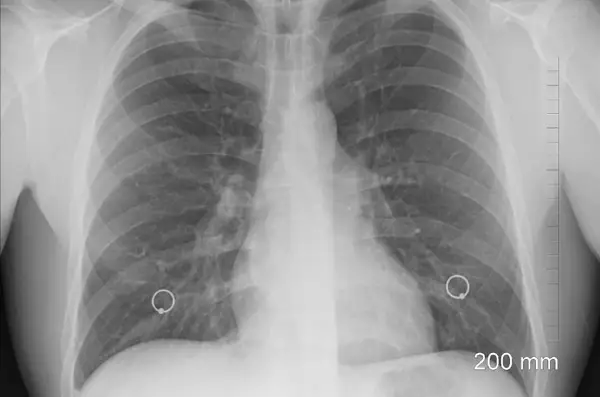

Ochorenia dýchacej sústavy sú treťou najčastejšou príčinou úmrtí, hneď po kardiovaskulárnych ochoreniach a rakovine. V rebríčku najčastejších príčin hospitalizácie sa nielen na Slovensku dlhodobo umiestňuje zápal pľúc - pneumónia.

Zápal pľúc je často spôsobený baktériou Streptococcus pneumoniae. Je to vážne ochorenie, ktoré môže byť život ohrozujúce. Najviac prípadov ochorenia sa vyskytuje v zime,

čo je spôsobené zníženou obranyschopnosťou organizmu, zvýšeným výskytom chorôb dýchacieho ústrojenstva a rýchlym a ľahkým prenosom baktérií kvapôčkami. Inkubačná

doba, tzn. čas od nákazy po vypuknutie prvých príznakov, sa odhaduje na 1 až 3 dni. Ide o infekčné ochorenie, tzn. že nie je možné zápal pľúc dostať len z prechladnutia.

Zápal pľúc postihuje 35 000 Slovákov ročne 3 , je jednou z najčastejších príčin hospitalizácie u nás a zároveň patrí medzi ochorenia s najdlhšou ošetrovacou dobou v nemocnici.